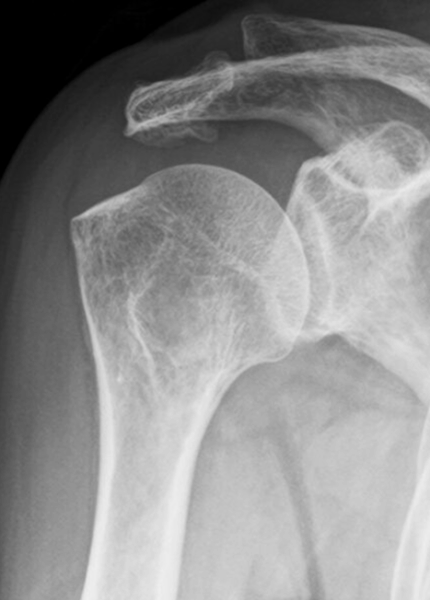

症例(60歳代女性)

2日前から右肩が急に痛み出し、夜も眠れない状態で来院。

レントゲンで石灰を確認し、エコーガイド下で吸引とステロイド注射を実施。直後から痛みは消失。

10日後、石灰は消失しました。

初診時のレントゲン:石灰が確認できます

10日後に石灰は完全に消失しています